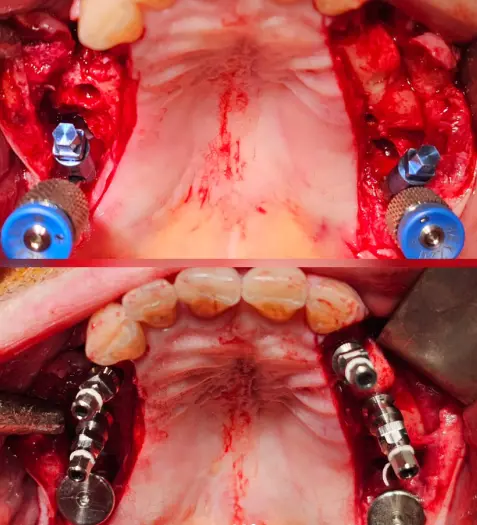

Cas clinique du Dr. Benat avec les implants Ptérygoïdiens

Le patient montre une insuffisance osseuse maxillaire postérieure bilatérale, objectivée sur la radiographie panoramique préopératoire, ne permettant pas la pose d’implants axiaux conventionnels sans solution de rattrapage d’axe.

Avec la collaboration du Dr. Gauthier Benat